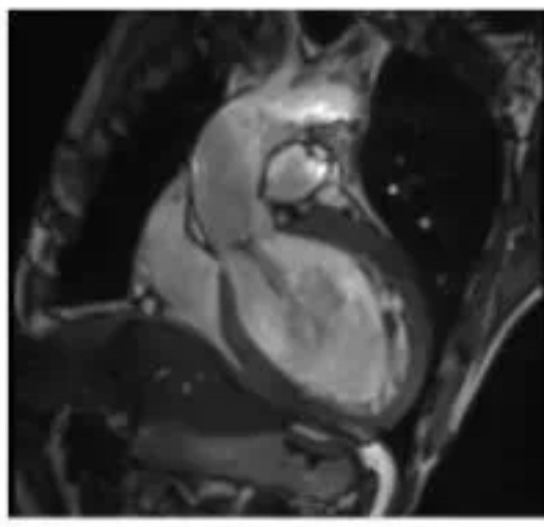

6、心臟CTA是經(jīng)靜脈注射造影劑后進(jìn)行CT快速掃描和圖像重建技術(shù)獲得冠狀動(dòng)脈圖像,以精準(zhǔn)了解冠狀動(dòng)脈是否存在解剖變異、畸形、心肌橋、狹窄,評(píng)估冠狀動(dòng)脈支架或搭橋術(shù)后血管情況等。心臟磁共振檢查具有無(wú)輻射、多參數(shù)、多平面、多序列成像等特點(diǎn),具有良好軟組織分辨力,一次檢查可獲得心臟解剖形態(tài)、心臟功能、血流、心肌灌注或活性、心臟代謝、大血管和冠狀動(dòng)脈的信息,在診斷心肌病方面具有重要意義。

心臟瓣膜病